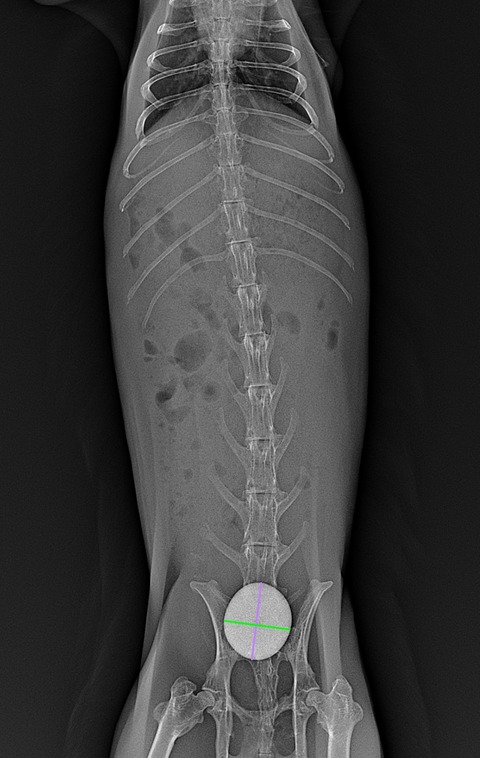

胃腸の内容物やガスの貯留具合は実際どうか、鬱滞を起こす原因となるようなものはないか(尿路結石や腹腔内腫瘍など)といったことを評価します

⇩巨大な膀胱結石が見られた症例